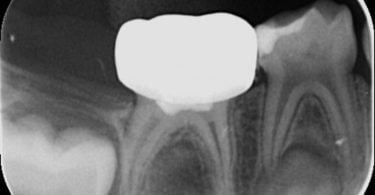

Foi realizado um exame clínico e radiológico inicial (fig. 1 a 3), tendo sido diagnosticada, entre outras lesões de cárie, uma lesão de cárie profunda com atingimento pulpar no segundo molar temporário inferior direito (fig. 3). Foi proposta a realização de uma pulpotomia com agregado trióxido mineral (MTA) e a colocação de uma coroa pré-formada. As várias possibilidades restauradoras foram apresentadas e discutidas com os pais, que decidiram optar pela colocação de uma coroa pré-formada de zircónia, por motivos estéticos.

No exame clínico e radiográfico realizado seis meses após o tratamento, não foi referido nenhum sintoma nem foram observados sinais indicadores de fracasso (fig. 10 e 11). Na radiografia periapical é possível observar a presença de pontes de dentina à entrada dos canais radiculares (fig. 11).

A utilização de MTA em pulpotomias de molares temporários apresenta uma elevadíssima taxa de sucesso observável no plano radiográfico pela ausência de imagens radiolúcidas na região apical e da furca radicular, e pela presença de pontes de dentina na entrada dos canais radiculares.7,8,9